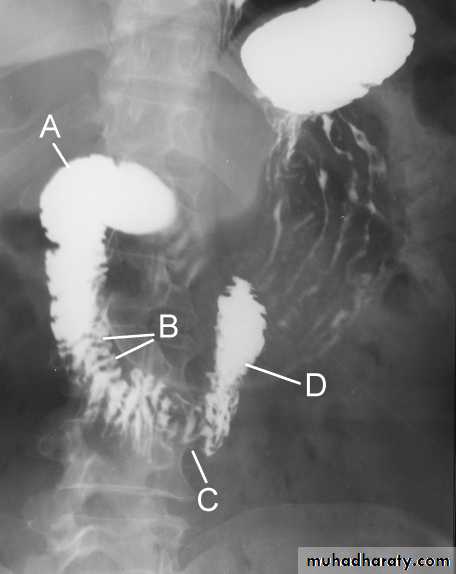

The Normal Anatomy of Stomach

GIT

1- Shape.2-Size.3-Site.4-Anatomical parts.5-Mucosal pattern.

Normal Anatomy of DuodenumA.Duodenal cap.

B.Duodenal loop